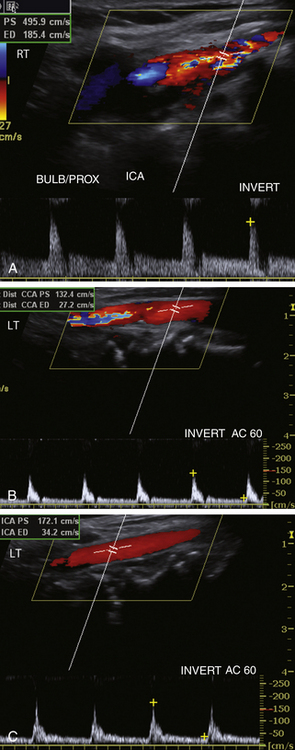

У этого 68-летнего мужчины появился шум в правой шее. Допплеровская оценка демонстрирует высокие скорости, приближающиеся к 500 см/сек в правой ВСА. Повышенные скорости отмечаются в левой общей и внутренней сонной артериях. Эти результаты показаны на рисунке 10-11 . Пожалуйста, ознакомьтесь с этой информацией и определите тяжесть стеноза левой ВСА.

РИСУНОК 10-11. Случай 1. A. Цветное изображение правой внутренней сонной артерии (ВСА) со спектральным отображением. B: Цветное изображение левой дистальной части общей сонной артерии (ОСА) с допплеровским спектром. C: Цветное изображение левой ВСА с доплеровским спектром.

Повышенная пиковая систолическая скорость (PSV; 496 см/сек) и конечно-диастолическая скорость (185 см/сек) соответствуют более чем 80% стенозу проксимальной правой ВСА. На первый взгляд, PSV (172 см/сек) в левой ВСА предполагает стеноз от 50% до 69%, но обратите внимание, что изображение цветового потока нормальное и не предполагает такого уровня сужения. PSV в дистальной левой ОСА составляет 132 см/сек. Если вы рассчитаете коэффициент PSV (ICA/CCA), вы получите 1,3, что значительно ниже уровня 2,0, который обычно наблюдается при сужении 50% и более. Причиной ложно высоких скоростей является контрлатеральный стеноз ВСА. ПСВ в ОСА значительно выше нормального уровня, который редко превышает 100 см/сек. Это явление называется компенсаторным кровотоком через нормальную или менее тяжело пораженную сонную артерию. В сонной артерии напротив стеноза или окклюзии высокой степени наблюдаются увеличенные PSV, которые кажутся непропорциональными степени сужения, определяемого при серой шкале и цветном допплеровском исследовании. Таким образом, соотношение систолических скоростей (ICA/CCA) лучше, чем только ICA PSV, при оценке тяжести стеноза. В этом случае левые сонные сосуды служат коллатералями, которые компенсируют уменьшенный кровоток в правой сонной артерии. Более высокий объем кровотока искажает все скорости вверх в левой сонной системе, включая скорость стеноза ВСА. Одним из важных ключей к диагностике компенсаторного кровотока является повышение PSV по всей контралатеральной ОСА и ВСА.

Диагностика

Стеноз правой проксимальной части ВСА высокой степени (более 80%) и стеноз левой ВСА менее 50% с увеличением скорости кровотока за счет коллатерализации (компенсаторный поток).

Что следует помнить

1. Состояния с высоким потоком, независимо от причины, увеличивают PSV, что может привести к завышению оценки тяжести стеноза.

2. Всегда смотрите на «общую картину», а не просто на изолированное измерение скорости. Просмотрите все измерения скорости для каждой сонной артерии. Подумайте о том, что происходит во всей каротидно-позвоночной системе, и помните, что изменение физиологии кровотока в одном сосуде может повлиять на результаты допплерографии в других сосудах.

3. Всегда учитывайте соотношение систолических скоростей при диагностике тяжести стеноза. Это особенно ценно для состояний с высоким и низким расходом.

4. Всегда сравнивайте результаты спектральной допплерографии, шкалы серого и цветового потока. Если они не совпадают, спросите себя: «Имеет ли это смысл?»